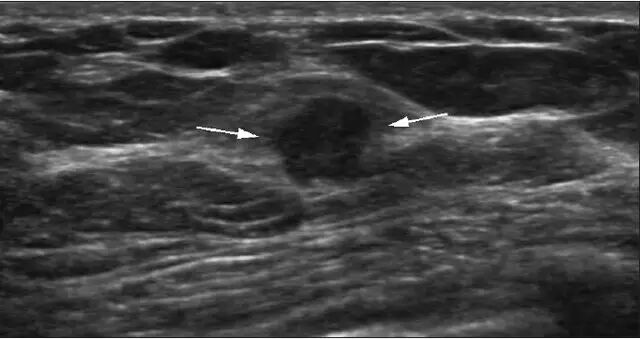

在随后的临床治疗中,53 个结节行传统外科手术切除,12 个结节行真空辅助下旋转切除术,13 个结节行 2 年以上超声随访未发现异常变化,最终视为良性病变(图 1 和图 2)。

穿刺枪怎么升级乳腺穿刺术(三)_https://www.jmylbn.com_新闻资讯_第59张图 2 一 45 岁女性因右乳疼痛就诊,超声发现左乳一 0.7 cm 结节,边界清晰,呈复杂囊性病灶,BI-RADS 分级为 4a 类;钼靶检查提示致密型乳腺;超声随访 27 个月后病灶增大至 1.3 cm(箭头所示),遂行外科手术切除,术后病理证实为不典型乳头状瘤

根据最终术后病理及随访结果,共发现有 6 个良性乳头状瘤升级为不典型乳头状瘤,2 个不典型乳头状瘤升级为导管内原位癌,这其中有 7 个术前超声 BI-RADS 分类与穿刺病理结果一致,1 个 BI-RADS 分类与穿刺病理结果不一致。统计学分析后,患者年龄、结节大小、结节与乳头距离、病灶是否多发等指标在结节分级升级组与稳定组间无统计学差异。

作者指出,该研究发现只有 2 例不典型乳腺结节升级为恶性结节,表明这类结节的恶性率较低(2/78)。因此,对于穿刺病理证实良性的乳腺隐匿性结节,可选择进行影像学随访或进行真空辅助下旋切术,而不一定要进行外科手术切除。